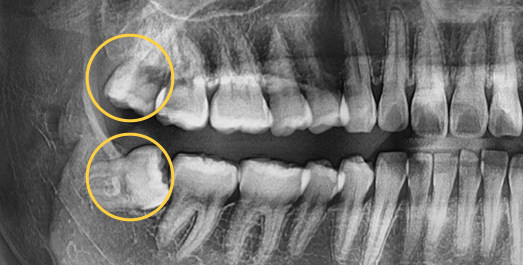

Even advanced cases

can be extracted.

With extensive experience in numerous advanced cases and a wide range of wisdom tooth extractions, you no longer need to go to a university hospital.

• BEFORE

• AFTER

Treatment Date : 2024.09.04

Treatment Date : 2023.12.22

Treatment Date : 2024.05.28